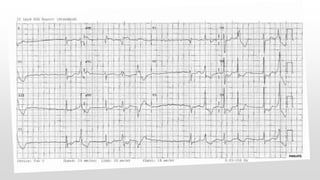

This document discusses various cases of collapse and syncope. It defines collapse as transient loss of consciousness with loss of postural tone and full recovery. Syncope is defined as loss of postural tone with or without loss of consciousness and full recovery. It then discusses the multiple potential causes of collapse and syncope including toxicological, cardiac conduction abnormalities, structural cardiac issues, autonomic dysfunction and more. It then goes through 9 case examples, discussing important questions to ask, potential tests and interventions for each case.